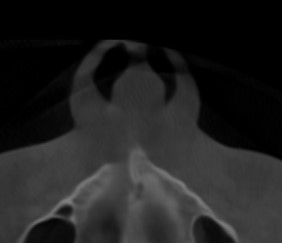

CBCT (Front + Side) + OPG (Old Before & New After braces) (need decompensation)

Septum + Palate

Disclaimer: I’ve done some preliminary measurements on my CBCT using RadiAnt and Romexis. I’m not a pro, so if I messed up some calculations, please let me know. These should be roughly accurate though.

My Analysis (Based on CBCT):

- Inter-molar Width: ~34.7mm (Narrow palate, teeth in compensation).